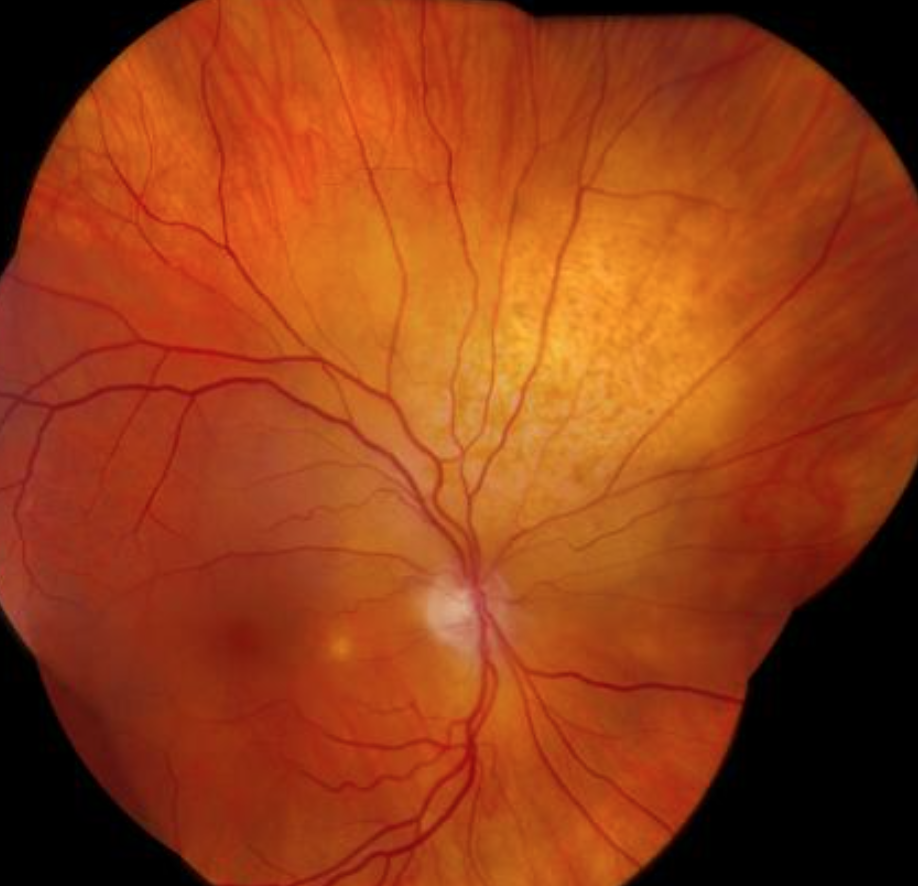

Coat’s disease signs?

Leukocoria

Telangectasia (abnormal dilated capilaries)

"Lightbulb" telangiectasia

Multiple clumped lipid exudates